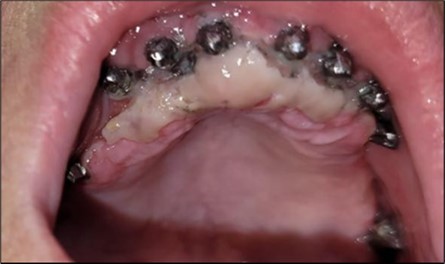

Plexus anesthesia is used in all working areas with Articaine 40 mg/0.01 mg/ml adrenaline. For mucosal disinfection, Betadine 10% is used.Two stage implants are removed either by simple extraction with forceps and an elevator or by using an osseous bur in cases where they cannot be easily removed using the first method. The remaining teeth are extracted, and the crest is regularized to avoid excessive future resorption, as well as to create an alveolar crest with a favourable resorption optical level for aesthetics (Figure 6, Figure 7).

In the upper anterior region, after extractions and regularization, marginal gingival connective tissue located palatine is harvested for use in augmenting the anterior area. This tissue is de-epithelized with a scalpel and kept in saline solution until used (Figure 4, Figure 5). The implants used are BCS corticobasal implants in areas with significant bone loss, and TPG compression implants, both from Dr. Ihde Dental AG, for post-extraction areas and regions with a large amount of trabecular bone but of poor quality (D3-D4). Both types of implants have a polished surface to reduce bacterial adhesion, and they feature a 2mm prosthetic collar that can be bent to parallelize the prosthetic part of the implant according to prosthetic requirements (Figure 3). The only exception to this parallelization through bending is the TPG implant in the maxillary-sphenoid fusion area (quadrant 2), were, due to lower torque, a prefabricated parallelization sleeve with a 25° angle was preferred. This sleeve was cemented before the impression was taken (Figure 3).

Considerations related to connective tissue grafting in post-extraction and post-implant defects – it is a technique that can be performed either by harvesting connective tissue from the tuberosity area, the palate, or the marginal palatal area, if the quantity is sufficient 11. It is done simultaneously with the rest of the bone regularization procedure; in this case, removal of the palatal gingival area was necessary anyway for easier cleaning and access to the frontal implants. On this occasion, after de-epithelialization, the tissue is used to restore the shape of the frontal gingival area after implant insertion (Figure 4, Figure 5).

Figure 4.Repair of the frontal area with connective tissue harvested from the marginal palatal area after extraction and crest regularization: (a) mucosal tissue piece harvested from the frontal palatal area before preparation; (b) prepared connective tissue piece placed between the frontal implants under the mobile mucosa.

Repair of the frontal area with connective tissue harvested from the marginal palatal area after extraction and crest regularization: (a) mucosal tissue piece harvested from the frontal palatal area before preparation; (b) prepared connective tissue piece placed between the frontal implants under the mobile mucosa.